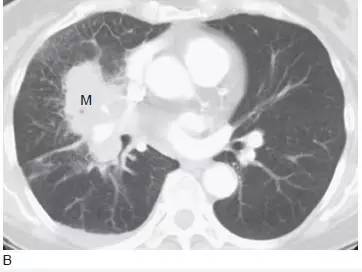

1、鳞状细胞癌

影像学表现常见息肉状腔内肿块和( 或) 支气管阻塞( 图1A)。肺门的肿块也很常见,这归因于肿瘤位于中心位置,可侵犯局部组织,累及肺门淋巴结( 图1B)。肺不张( 图2)、实变、黏液嵌塞和支气管扩张常见, 提示支气管阻塞。只有30%的鳞癌表现为肺外围结节。中央坏死和空洞( 图3) 较其他类型肺癌更常见。

图1 表现为支气管管腔内和肺门肿块的鳞状细胞癌

A.CT 显示右下叶支气管内息肉状的肿块( 箭头),为典型的鳞状细胞癌;

B. 在稍低层面,支气管腔阻塞伴局部浸润,导致肺门肿块(M)